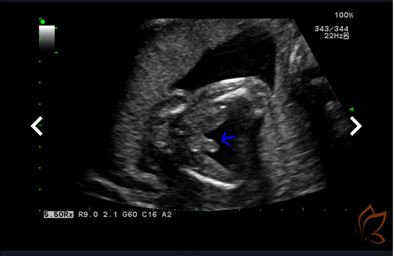

• 第十六周 & 性別揭曉派對